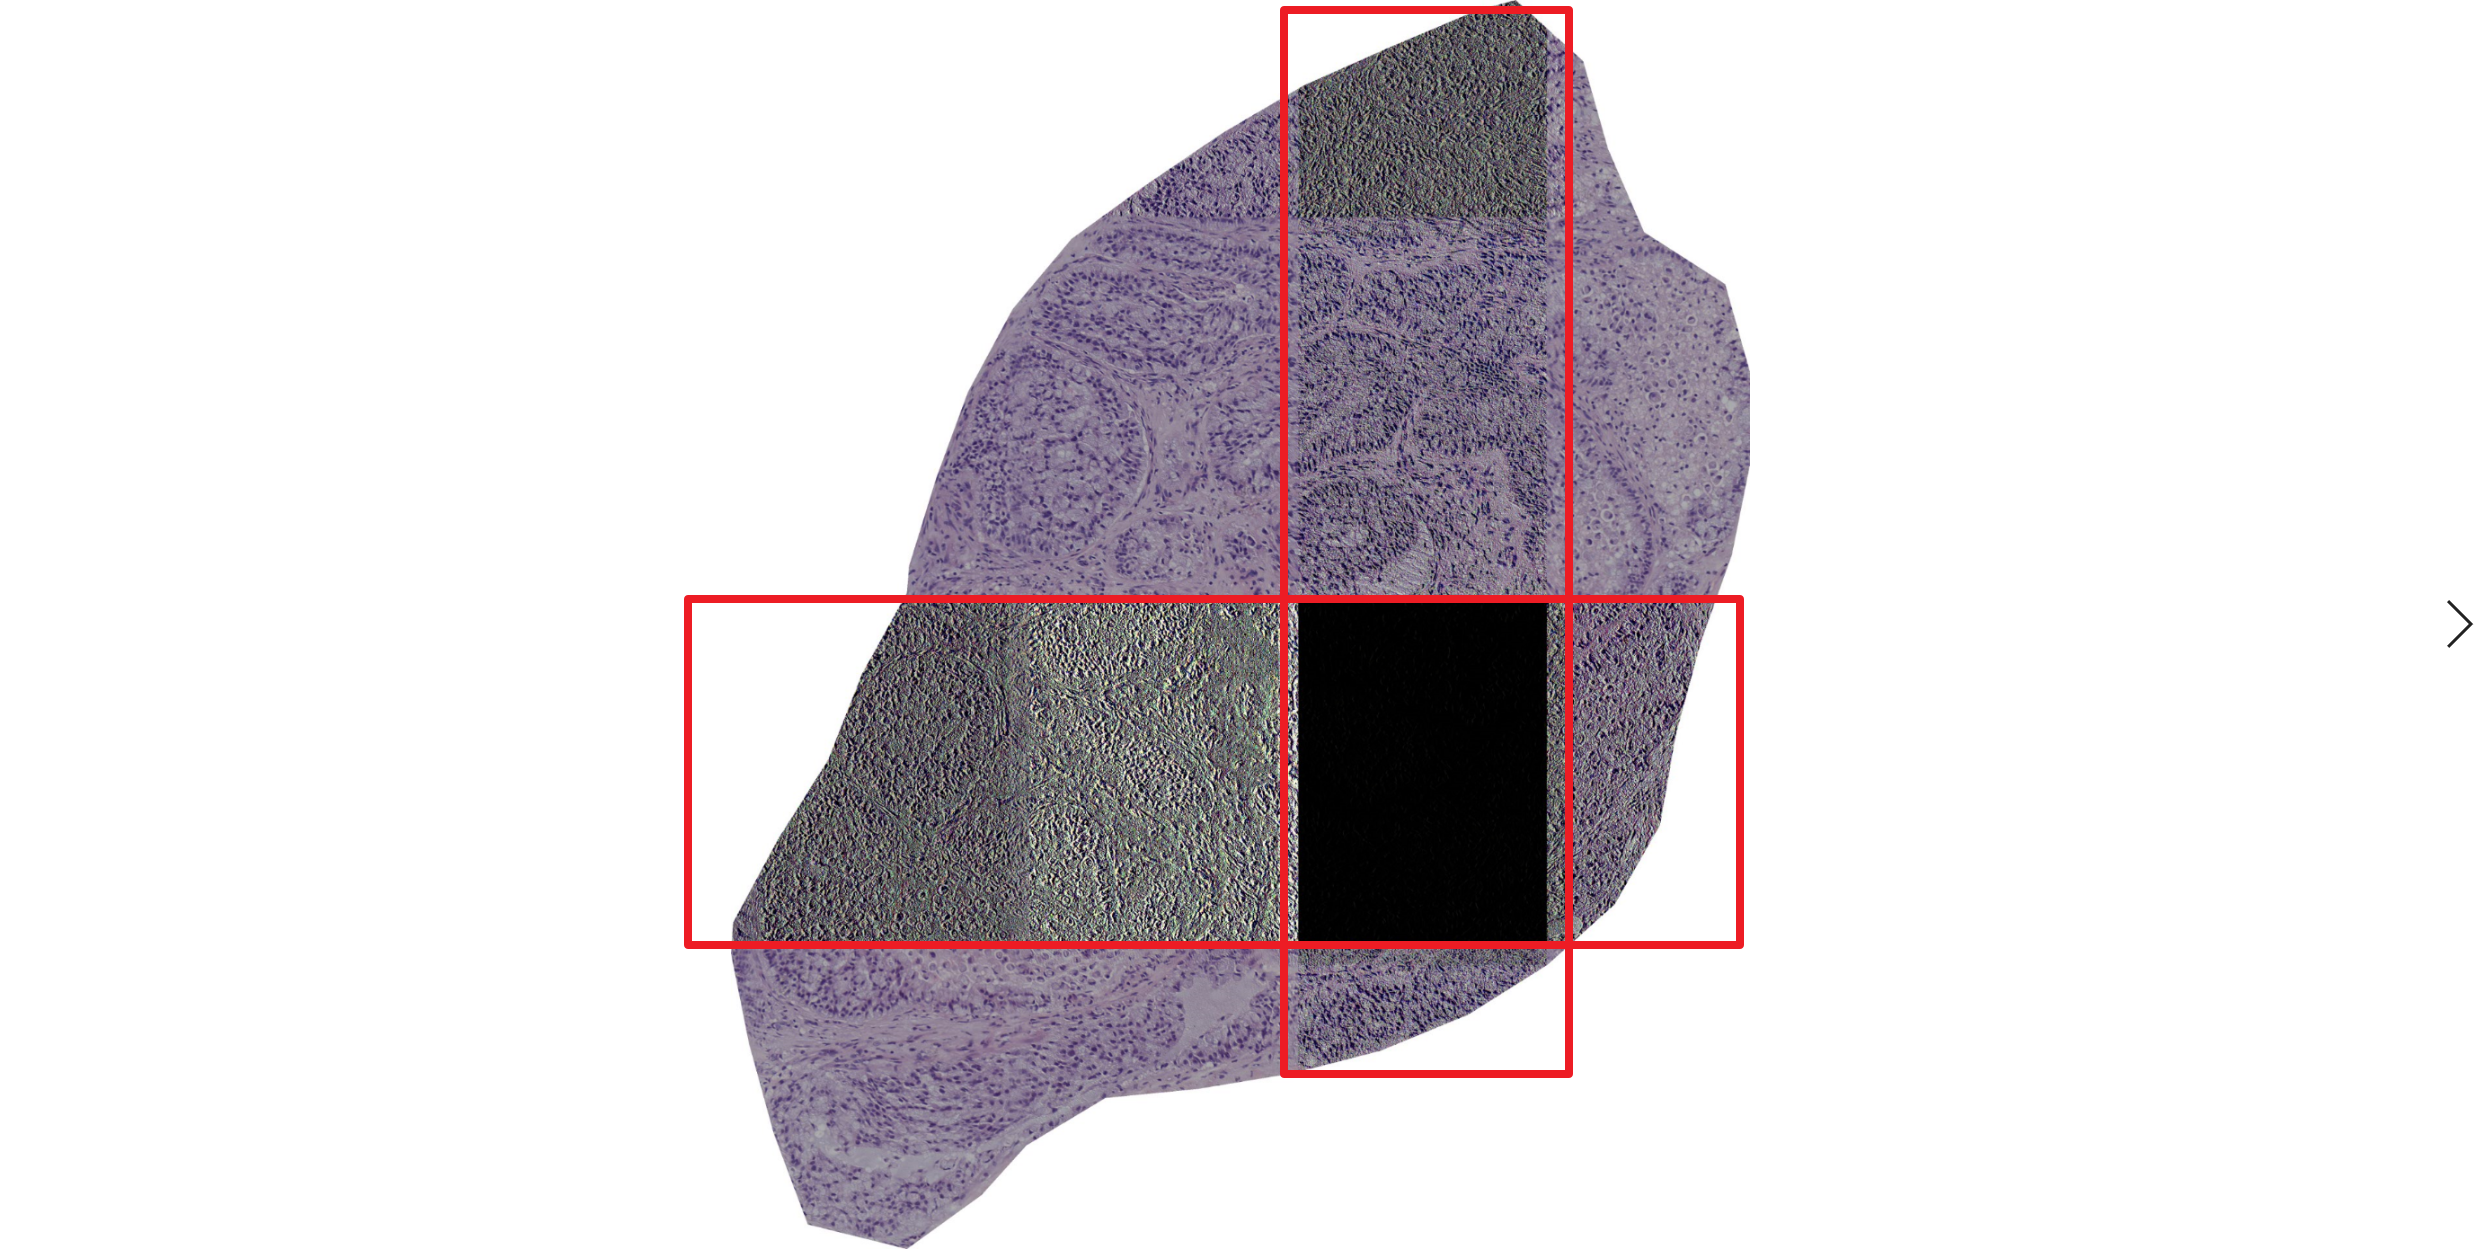

Encountered image distortion after reading with `slide.read_region()`

Encountered image distortion after reading with slide.read_region(), is there any solutions?